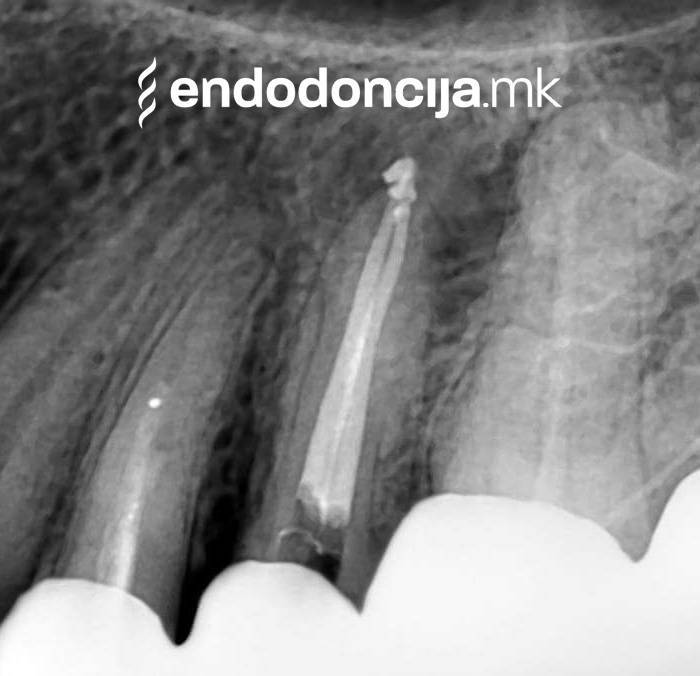

Κατά τη διάρκεια προηγούμενων θεραπειών, το δόντι μπορεί όχι μόνο να έχει αποδυναμωθεί από τη μηχανική επεξεργασία του ριζικού σωλήνα αλλά και από τη στερέωση και την αγκύρωση ενός ρίζα. Όταν αναθεωρείται η επεξεργασία ενός ριζικού καναλιού, αυτοί οι πείροι πρέπει να αφαιρούνται όσο το δυνατόν πιο προσεκτικά για να διατηρούν σημαντική ουσία των δοντιών.